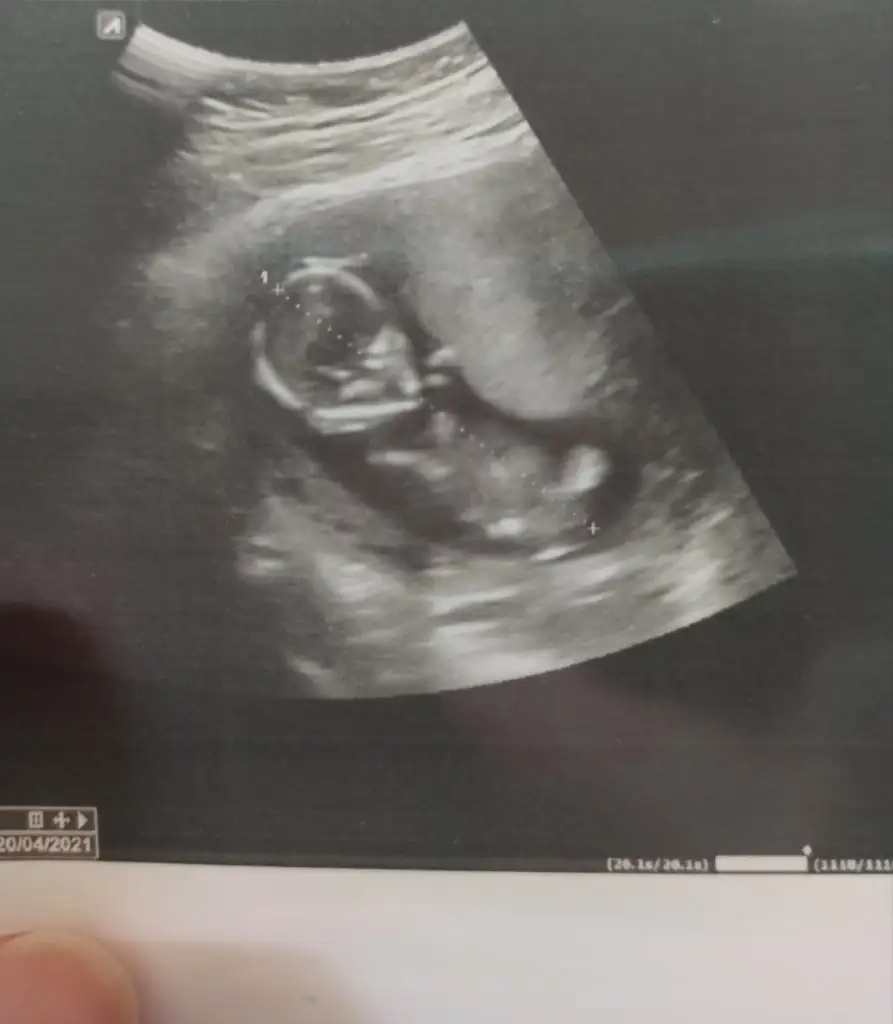

11 12 13 haftalar olmalı sanki kız gibi gibi istediğim haftalar varsa paylaşınBana da tahminde bulunabilir misinizz 14 haftalıkEki Görüntüle 2708872

Erkek gibi sanki